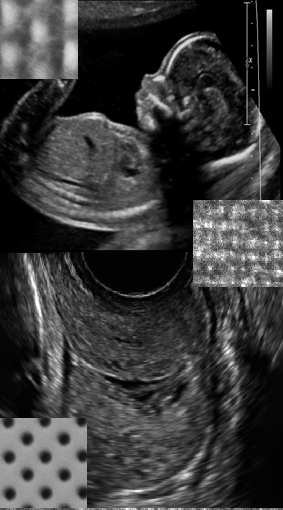

La inducción del parto es una de las causas más importantes del incremento de la tasa de cesáreas hoy en día. Aproximadamente, de los 450.000 partos que hubo en España en 2012, 135.000 fueron inducidos. Así, la inducción se ha convertido en uno de los retos de la obstetricia moderna y motivo de debate científico. El sistema empleado actualmente para la predicción del éxito de la inducción se basa en la evaluación cervical. Aunque dicho sistema es un aspecto clave en el equilibrio riesgo-beneficio clínico, es un modelo clásico y con demostrada escasa capacidad de predicción. La información extraíble del cérvix uterino mediante palpación es insuficiente para seleccionar de forma precisa la mejor técnica de inducción del parto en cada caso. Si bien varios grupos de investigación han estudiado otras variables y han demostrado que tienen mejor capacidad de predicción, no hay un acuerdo entre la comunidad científica de cuál es el mejor sistema que pueda sustituir al actual.

Analizar las imágenes ultrasónicas del cérvix de una mujer gestante, obtenidas en el momento previo a la inducción del parto, permitiría el desarrollo de modelos predictivos más válidos y precisos que facilitarían una mayor personalización de su tratamiento y manejo clínico. Dicho sistema podría ser determinante para predecir con mayor probabilidad de éxito que estrategia de inducción provocaría el parto natural y así reducir el número de cesáreas.

En este contexto, el proyecto ALTAIR tiene como primer objetivo analizar la textura del cérvix uterino a partir de la ecografía para asistir al obstetra en la determinación del método de inducción al parto óptimo para cada paciente, reduciendo el número de cesáreas y beneficiando notablemente tanto la salud de la mujer gestante como la del neonato. Esta parte del proyecto se realizará en colaboración entre el centro tecnológico Vicomtech y BioCruces, quien proporcionará a Vicomtech los datos de pacientes necesarios tanto para la implementación del modelo predictivo como para su validación.